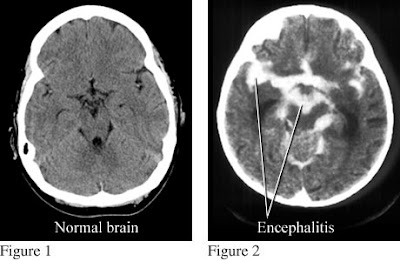

Η διάγνωση της νόσου γίνεται μέσω αιματολογικών εξετάσεων, ακτινολογικών και παθολογοανατομικών. Μπορεί να χρειαστούν και εξετάσεις όπως ακτινογραφία, μαγνητική τομογραφία εγκεφάλου, αξονική τομογραφία εγκεφάλου, εξετάσεις αίματος, εξετάσεις ούρων, καλλιέργεια πτυέλων, ηλεκτροεγκεφαλογράφημα, οσφυϊκή παρακέντηση (δηλαδή με μία ειδική βελόνα αντλείται υγρό από τη σπονδυλική στήλη) και τέλος βιοψία εγκεφάλου.

Η εγκεφαλίτιδα πρόκειται για φλεγμονή του εγκεφάλου, που προκαλείται από ιό και επηρεάζει τη ροή του αίματος προς τον εγκέφαλο. Είναι η φλεγμονή του εγκεφαλικού παρεγχύματος Μπορεί να είναι διάχυτη ή εστιακή (σπανιότερα). Συχνά συνυπάρχει και μηνιγγίτιδα. Η εγκεφαλίτιδα μπορεί να προκαλέσει γριππώδη συμπτώματα, όπως πυρετό ή πονοκέφαλο. Μπορεί επίσης να προκαλέσει σύγχυση σκέψης, επιληπτικές κρίσεις, ή προβλήματα με τις αισθήσεις και την κίνηση. Ωστόσο, πολλές περιπτώσεις εγκεφαλίτιδας καταλήγουν μόνο με ήπια γριππώδη συμπτώματα ή ακόμα και καθόλου συμπτώματα, γι’ αυτό και θέλουν ιδιαίτερη προσοχή.